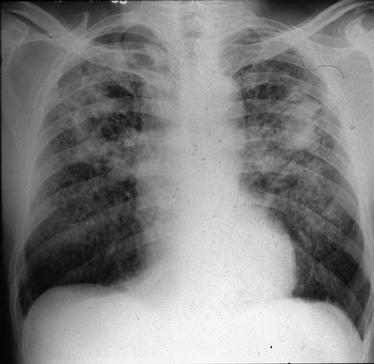

A 42-year-old man comes to the physician because of intermittent lower abdominal pain, diarrhea, and a 6.8-kg (15-lb) weight loss during the past year. He says that he tires easily. During the past 2 years, he has had a recurrent perirectal abscess treated with antibiotic therapy. Currently, his only medication is a daily multivitamin. He does not appear to be in acute distress. He is 180 cm (5 ft 11 in) tall and weighs 79 kg (175 lb); BMI is 24 kg/m2. His temperature is 37.2°C (99°F), pulse is 84/min, respirations are 16/min, and blood pressure is 145/75 mm Hg. Cardiopulmonary examination shows no abnormalities. A mildly tender abdominal mass is palpated in the right lower quadrant. Results of a barium enema are shown. Which of the following is the most likely diagnosis?